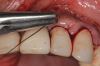

This is where the treatment became challenging. First, a curette was used to attempt to remove the granulation tissue from around the apex of the implant circumferentially. This was a difficult endeavor, especially on the palatal aspect of the site. Following curettage, an 810 nm diode laser (NV® PRO3, DenMat [alternatively: Picasso+, AMD Lasers; Gemini, Ultradent]) was used to treat the apical portion of the implant. After the laser tip was initiated using dark occlusal paper (Figure 4), it was used to debride the remaining necrotic tissue and decontaminate the entire site, reducing the bacterial count (Figure 5 and Figure 6).

(4.) The diode laser tip was initiated with dark blue occlusal paper.

Figure 4